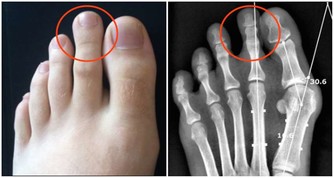

除非你認為自己真的有維生素缺乏症,比如你像躲避瘟疫一樣躲避陽光,就可能缺乏維生素D,這種時候,如果想要購買膳食補充劑,最好去驗血,看你是否真的缺乏,然後再遵醫囑服用。